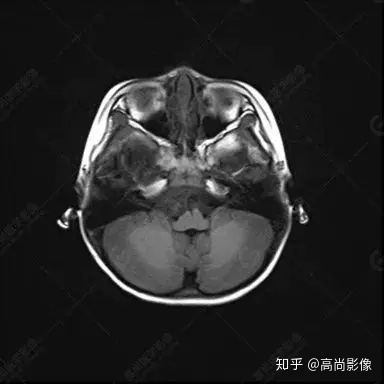

右側(cè)顳葉腫瘤切除術(shù)后(具體不詳):右側(cè)顳部骨質(zhì)不連續(xù)呈術(shù)后改變,右側(cè)顳葉術(shù)區(qū)見片狀長T1長T2信號影,F(xiàn)LAIR呈低信號;術(shù)區(qū)后方右側(cè)顳枕葉見一巨大占位性病變影,邊界欠清,大小約6.2×5.8×4.3cm(前后×左右×上下),信號不均勻,T1WI呈等稍低信號間雜少許高信號,T2WI呈高稍低混雜信號,DWI示部分病灶彌散受限,相應(yīng)ADC圖減低,磁敏感序列見部分呈極低信號,增強(qiáng)掃描可見明顯不均勻強(qiáng)化,鄰近硬腦膜及小腦幕增厚并明顯強(qiáng)化;另延髓右前方及右側(cè)橋小腦角區(qū)見一不規(guī)則形異常信號影,大小約3.2×1.3×3.7cm(左右×前后×上下),呈長T1稍長T2信號,F(xiàn)LAIR呈等信號,DWI未見受限,增強(qiáng)后明顯均勻強(qiáng)化,鄰近腦膜明顯強(qiáng)化。鄰近腦實質(zhì)及右側(cè)顳角明顯受壓;左側(cè)大腦半球未見局灶性信號異常,中線結(jié)構(gòu)稍左移。

右側(cè)顳葉腫瘤切除術(shù)后:現(xiàn)術(shù)區(qū)后方右側(cè)顳枕葉及延髓右前方占位,右側(cè)顳枕部硬腦膜及小腦幕明顯強(qiáng)化,結(jié)合既往影像資料,考慮為胚胎源性惡性腫瘤,如非典型畸胎樣/橫紋肌樣瘤(AT/RT)或原始神經(jīng)外胚層腫瘤(PNET)。

非典型畸胎樣/橫紋肌樣瘤(AT/RT) 是一種高度惡性中樞神經(jīng)系統(tǒng)腫瘤,臨床罕見,臨床表現(xiàn)無特異性,好發(fā)于 5 歲以下兒童,尤以 3 歲以下多見,在兒童原發(fā)性中樞神經(jīng)系統(tǒng)(CNS)腫瘤中占 1%~3%。該腫瘤體積一般較大,幕上大于幕下,有明顯的占位效應(yīng)。該腫瘤成分復(fù)雜,囊變、出血、壞死常見。因此 AT/RT信號混雜,囊性部分呈 T1WI低、T2WI高信號,增強(qiáng)后不強(qiáng)化;若瘤體出血,囊內(nèi)可見T1WI稍高信號、T2WI低信號,實性部分在 T1WI上呈混雜等、低信號,在T2WI 及 T2-FLAIR上呈混雜等高信號,增強(qiáng)掃描后大部分呈環(huán)形條帶樣明顯強(qiáng)化,中心壞死區(qū)不強(qiáng)化。另外,該腫瘤實性成分在DWI上呈高信號,說明腫瘤細(xì)胞核密集,水分子擴(kuò)散明顯受限,提示該腫瘤惡性程度高,容易復(fù)發(fā)及轉(zhuǎn)移。